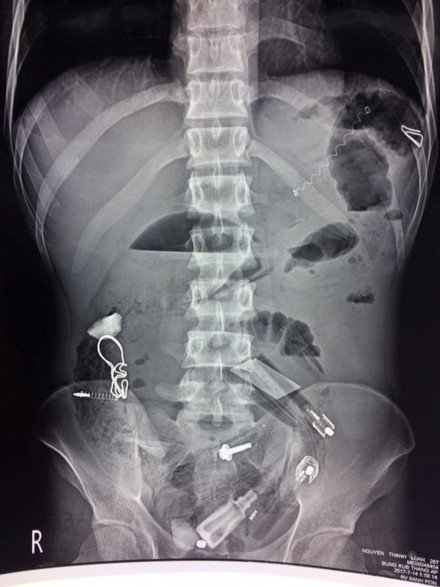

| Các bác sĩ chụp X-quang và phát hiện rất nhiều dị vật trong cơ thể bệnh nhân. |

Trước đó, sáng 15/7, bệnh viên tiếp nhận bệnh nhân có biểu hiện chướng bụng, mê sảng. Kết quả chụp X-quang cho thấy, trong dạ dày bệnh nhân có rất nhiều dị vật nên chỉ định phẫu thuật. Trong quá trình thực hiện, các bác sĩ đã lấy ra rất nhiều dị vật như bật lửa, lò xo bút bi, bút bi, thìa nhựa, lá cây, vỏ kẹo, vỏ thuốc, đinh…, tổng cộng hơn 30 dị vật.